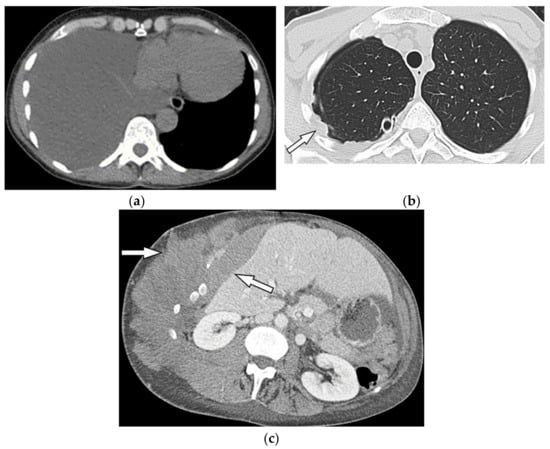

11.3. Mesothelioma

Malignant mesothelioma is the most common primary tumor of the pleura, which is related to prior asbestos exposure with a relatively poor prognosis [56].

Multidetector CT effectively reveals the primary tumoral extension, lymphadenopathy, and extrathoracic metastasis (Figure 27 and Figure 28) [56]. Another CT finding is circumferential pleural thickening (most common finding) with extension along the fissures. Large or punctate osseous or cartilaginous differentiation is more in favor of malignant mesothelioma rather than linear calcification that usually occurs within asbestosis plaques. Dynamic contrast-enhanced computed tomography (DCE CT) enables measuring intratumoral capillary permeability and blood flow, which are beneficial in evaluating treatment response [56,57,58].

Figure 27.

A 67-year-old man with dyspnea and chest pain. Contrast-enhanced CT in axial (a) and coronal (b) planes demonstrate left-sided localized enhancing pleural mass (arrow) with internal areas of necrosis that extend to the posteromedial aspect of the chest wall. Involvement of diaphragmatic pleura and elevation of left hemidiaphragm are also identified.

Figure 28.

A 70-year-old man with dyspnea. The non-contrast CT in the axial plane demonstrates right-sided large pleural effusion, near complete collapse of the right lung (a) after the chest tube insertion; thick circumferential nodular pleural thickening of parietal pleura was shown (arrow) (b). Contrast-enhanced CT of the upper abdomen shows the extension of mesothelioma through the abdominal cavity and wall with indentation over adjacent liver parenchyma (arrow) (c).

MR imaging and 18F-FDG PET/CT are useful in further evaluation of chest wall, diaphragm, and mediastinal invasion [56,57,58,59]. Malignant mesothelioma appears as unilateral hyperintense pleural effusion and pleural thickening with iso to slight hyperintensity to chest wall muscles on T1-weighted and moderate hyperintensity on T2-weighted images. Post-contrast enhancement is expected (Table 3). It is believed that higher metabolic activity on 18F-FDG PET/CT is associated with poor prognosis and shorter survival time [25,56,57,58].